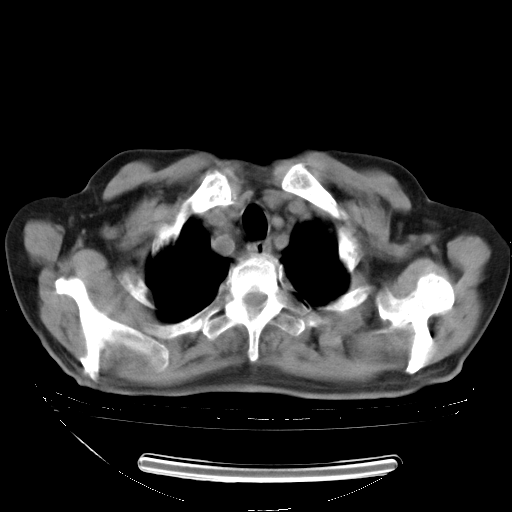

胸腹部CT,诊断意见:左上肺叶钙化灶、左侧胸膜局限性增厚并钙化、胆囊炎。描述部分肺组织呈磨玻璃样改变。